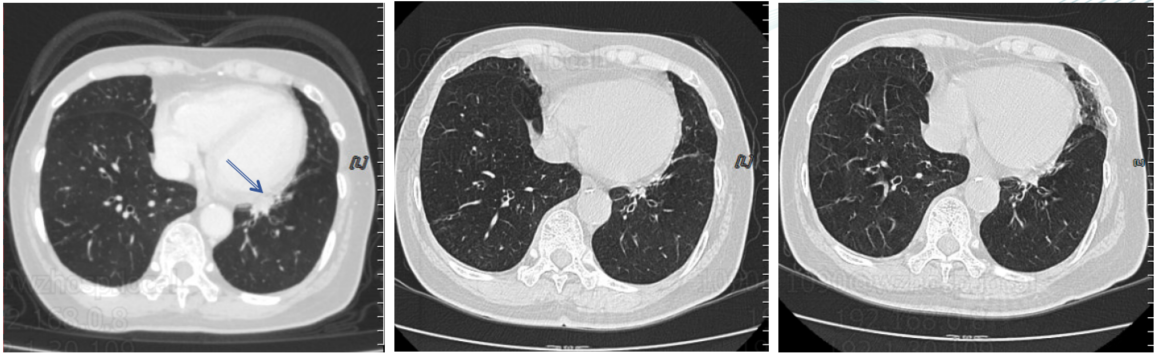

胸部CT(2023年11月10日):左肺下叶纵隔旁团块状病灶,径约21mm*30 mm。

图片1.png

胸部CT基线(2023年11月10日)

图片4.png

胸部CT(左:2023年11月12日;右:2024年5月24日)

胸部CT(左:2025年4月2日;中:2025年7月7日;右:2025年10月10日)